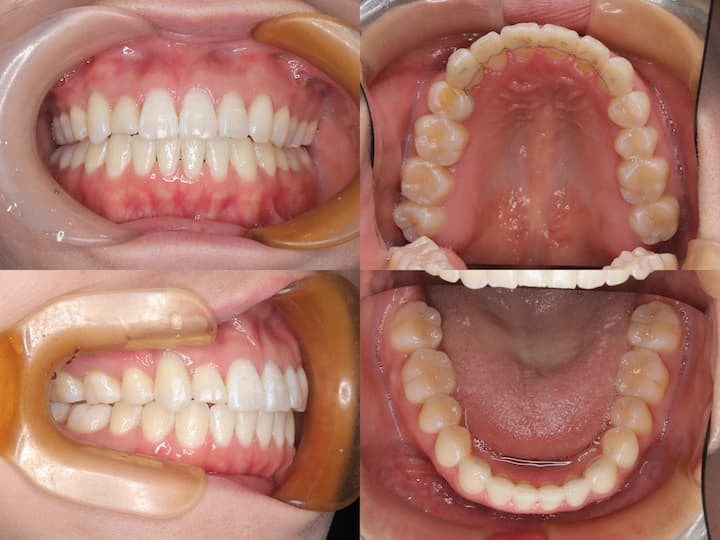

治療結果

上顎大臼歯の圧下により下顎骨のアンチクロックワイズローテーションが誘導され、口唇部の突出感は著明に改善されました。また、叢生も解消され、AngleⅠ級臼歯関係を維持したまま、機能的かつ審美的に優れた咬合状態を獲得することができました。

臼歯部の咬合も良好に保たれ、患者様からも高い満足度をいただいております。

本症例は、下顎骨の後方位を伴うハイアングル症例であり、口唇部の突出感が主訴の一つでした。このような症例では、上顎大臼歯の圧下による下顎骨のアンチクロックワイズローテーションが有効な治療戦略となります。

i-stationを用いた確実な固定源の確保と、フルサイズTMAワイヤーおよびパラタルバーによる緻密な咬合管理により、臼歯部のオープンバイトを生じることなく、大臼歯の圧下を達成することができました。

その結果、AngleⅠ級臼歯関係を維持しながら、口唇部の突出感を改善し、優れた治療結果を得ることができた症例です。